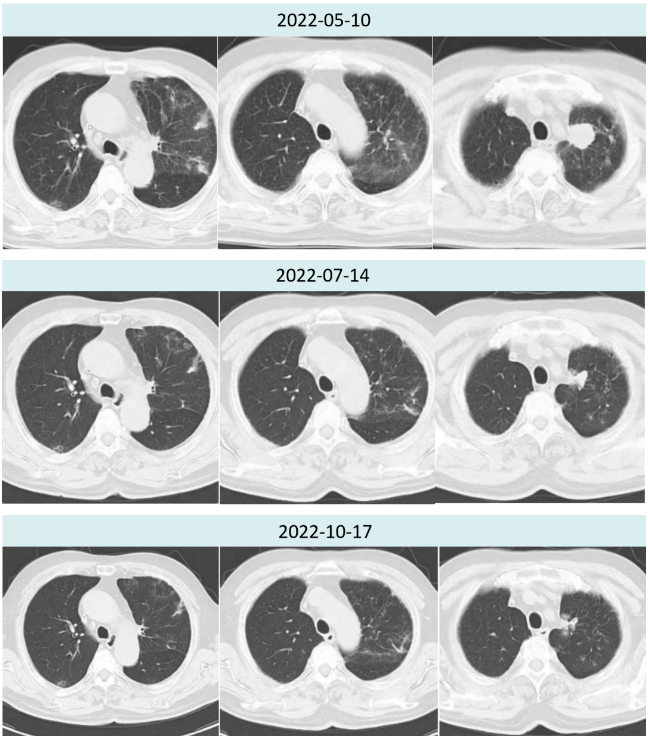

2022年5月10日胸部CT疗评进展(2.2cm→2.9cm)后,建议患者改三线化疗,患者拒绝。

2022年7月14日斯鲁利单抗联合安罗替尼治疗两周期后,胸部CT提示肿瘤病灶较前再次缩小,疗效评价PR(2.9cm→1.6cm),且两肺间质性炎症较前好转。

2022年10月17日斯鲁利单抗联合安罗替尼治疗六周期后,胸部CT提示肿瘤病灶较前继续缩小,疗效评价持续PR(2.9cm→1.4cm)。

图3.患者治疗前后胸部病灶及肺炎情况对比

该例患者为广泛期小细胞肺癌,依据2021年CSCO小细胞肺癌诊疗指南及NCCN指南推荐,一线应用度伐利尤单抗联合EC方案化疗,疗效佳,但很快出现2级免疫性肺炎。二线安罗替尼治疗期间,肿瘤退缩不明显。2022年ASCO大会口头报道的ASTRUM-005研究中斯鲁利单抗有较好的安全性,后线尝试斯鲁利单抗联合安罗替尼治疗,令人惊喜的是,肿瘤出现明显退缩,2周期后影像学检查提示疗效即达到PR,疗效显著。

在应用斯鲁利单抗伊始,CT显示该患者间质性肺炎仍未完全消退,使用斯鲁利单抗治疗期间未出现间质性肺炎加重或其他免疫不良反应。目前患者已应用斯鲁利单抗联合安罗替尼治疗6周期,持续PR大于4月。我们将继续跟进患者疗效与不良反应发生情况,期待为患者带来长久生存获益。